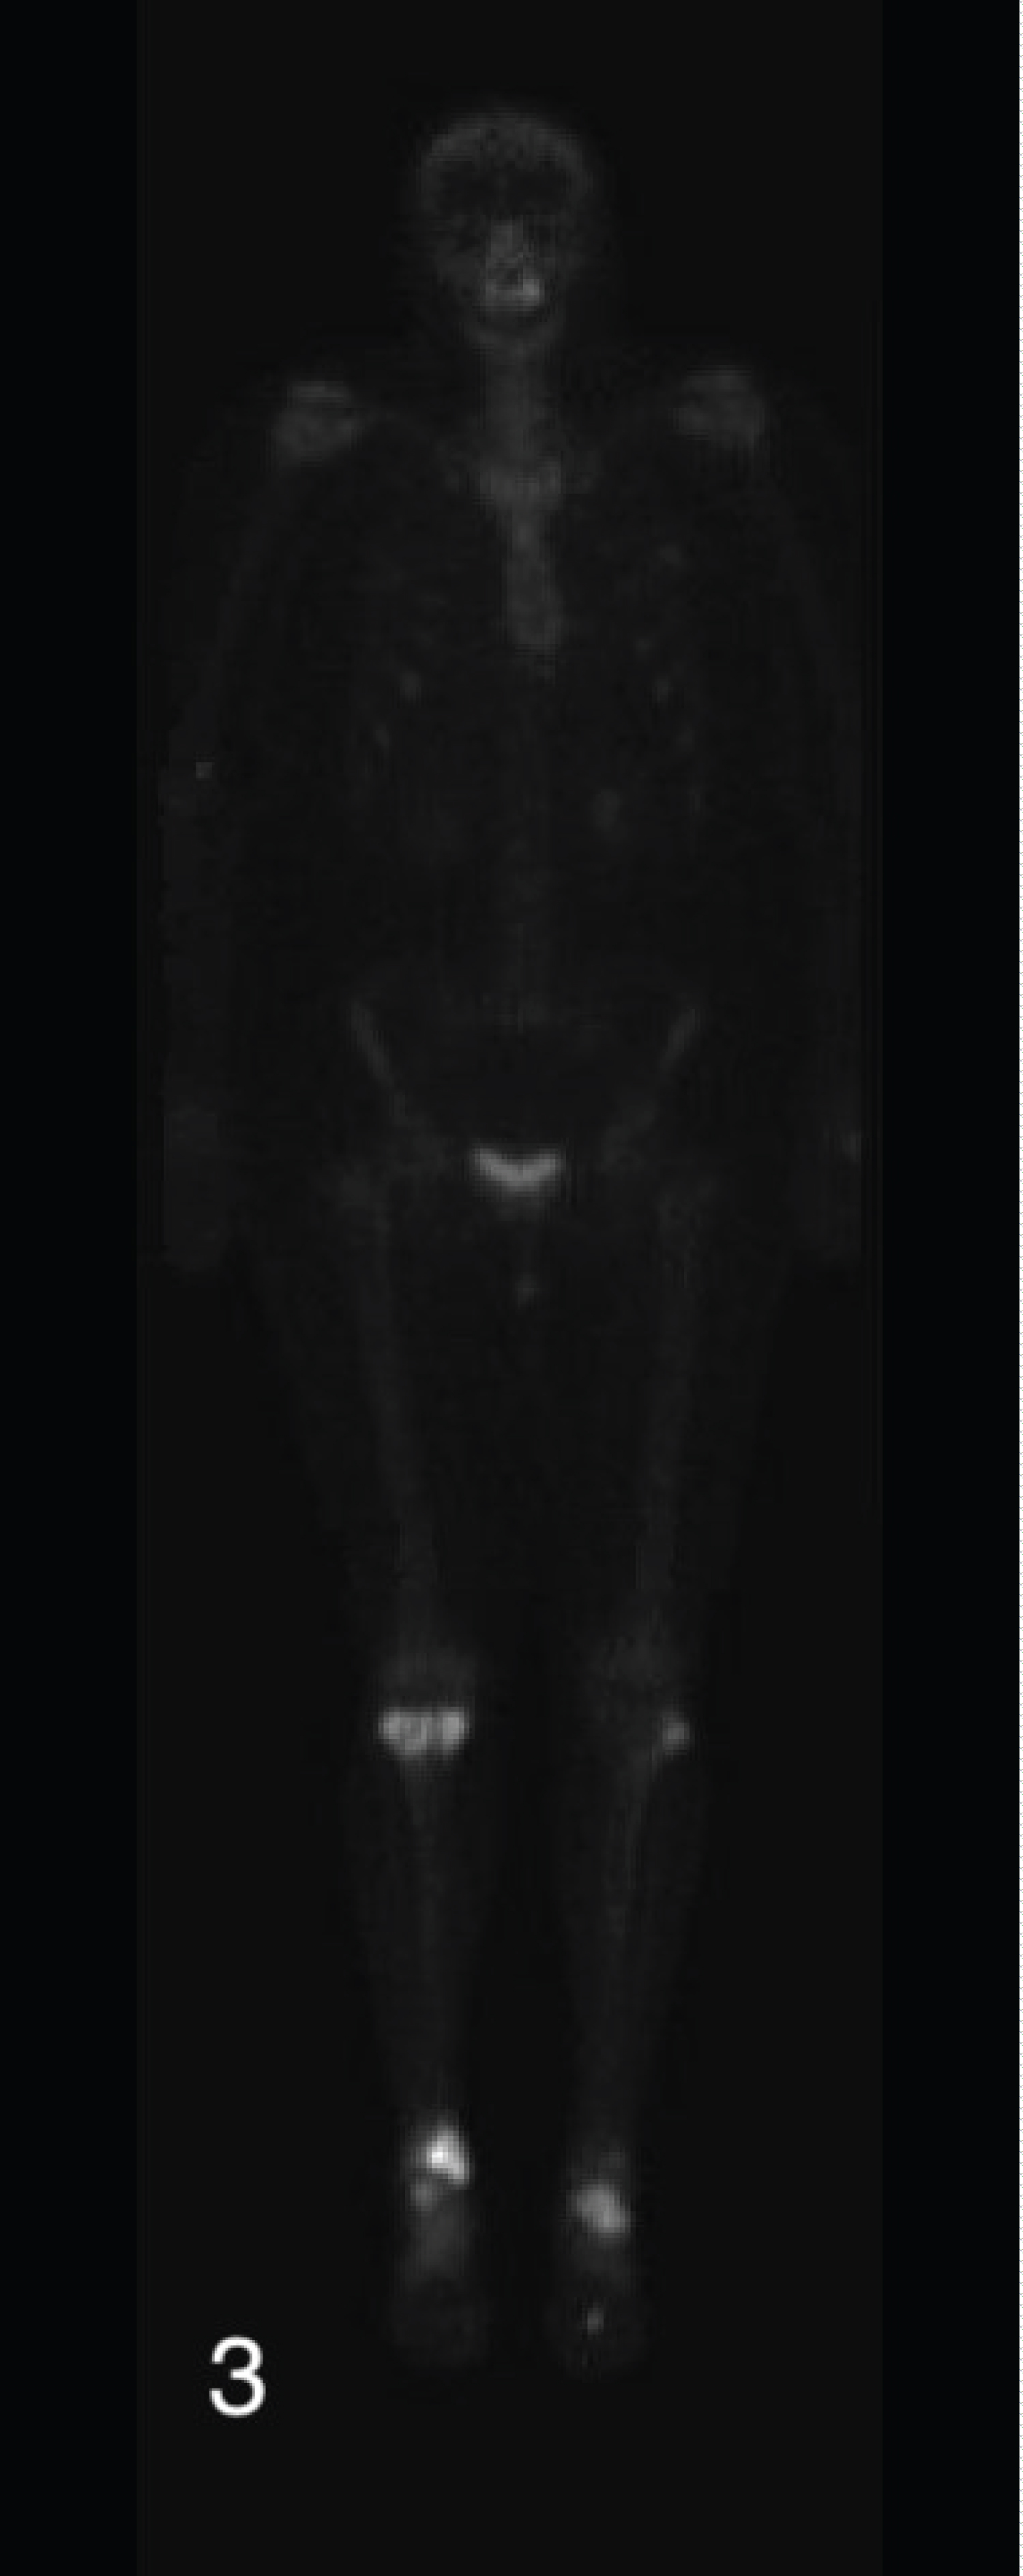

Conventional radiographs demonstrated a lytic bony lesion in the right medial malleolus (Figure 1). Magnetic resonance imaging (MRI) demonstrated a contrast enhancing marrow replacement lesion in the medial malleolus as well as the lateral calcaneus (Figure 2). Whole body bone scan demonstrated multiple lesions throughout the bilateral lower extremites (Figure 3).

Figure 3: Whole body bone scan demonstrating multiple lesions in the bilateral lower extremities. View Figure 3